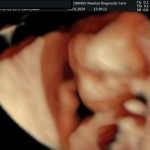

- De la edad gestacional (precisión en el cálculo del tiempo de embarazo).

- Crecimiento fetal.